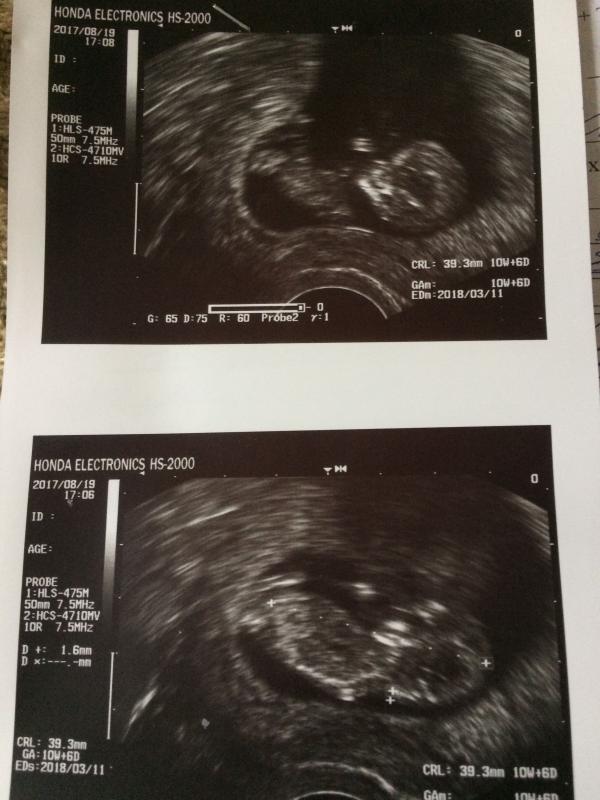

Неужели на 10 неделях так видно ребеночка)))